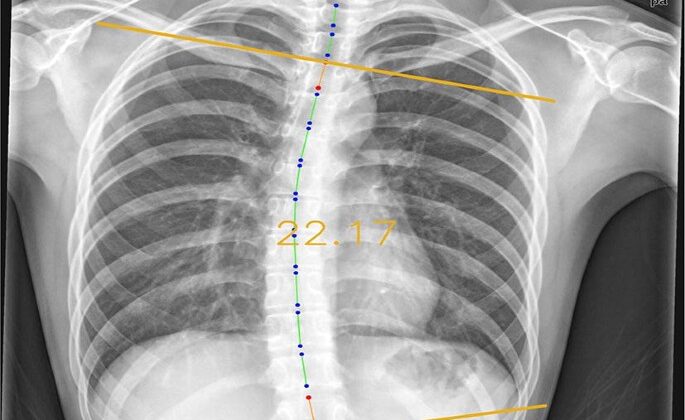

درجة اعوجاج العمود الفقري تُقاس باستخدام زاوية كوب (Cobb Angle)، وهي المعيار الطبي المعتمد عالميًا لتحديد شدة الانحناء من خلال الأشعة السينية.

كلما زادت زاوية كوب، زادت شدة الاعوجاج، وارتفعت احتمالية تطوره وتأثيره على صحة الطفل أو المريض.